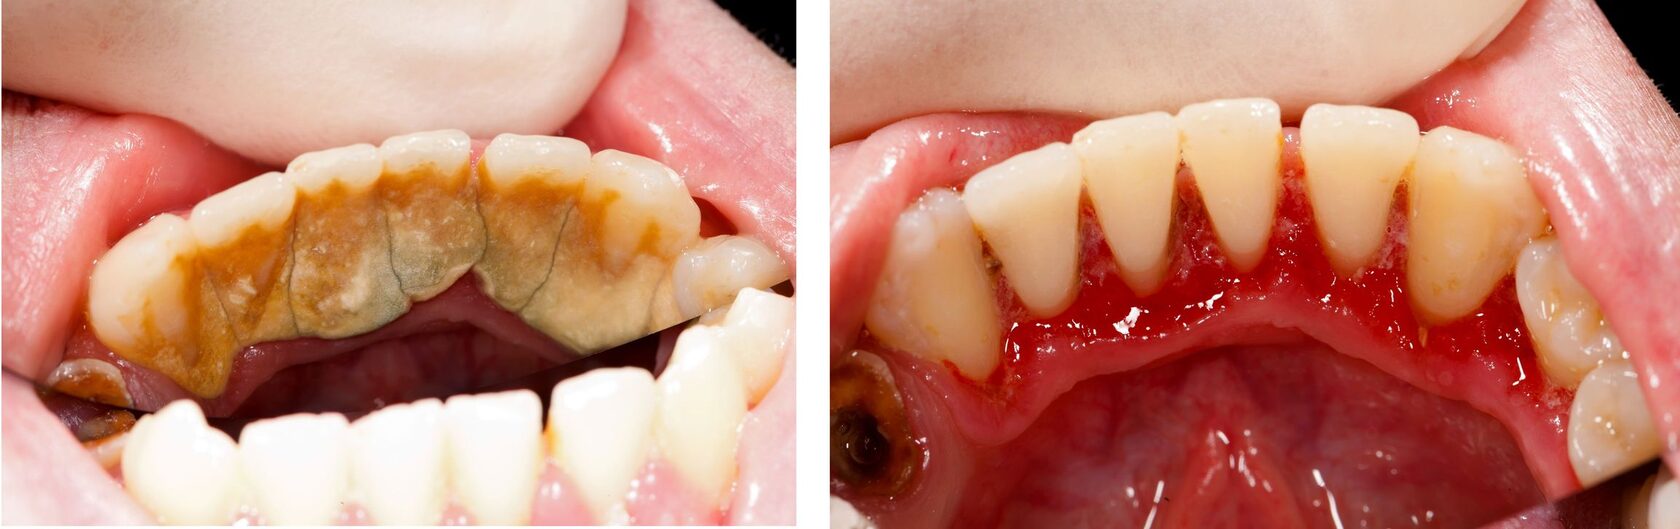

Травматический периодонтит: фото до и после